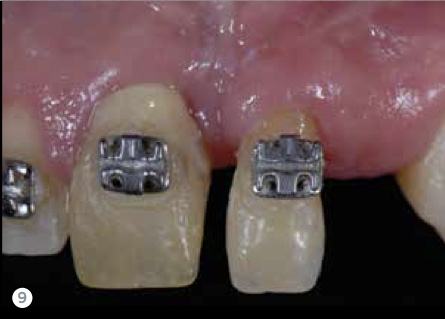

Risk is the potential that a chosen action or activity, including the choice of inaction, will lead to a loss or undesirable outcome. It includes any threat that the patient or clinician could potentially encounter. In dentistry, it takes seconds to destroy and years to reconstruct (Figure 8 and Figure 9), and this reality can be the greatest threat to reconstruction and implant-supported prostheses. When assessing risks, examining the patient through several different risk filters provides a holistic view of the patient’s condition. A patient’s risk may be present in one or many of these filters.

Fig 8 It takes seconds to destroy and sometimes years to reconstruct. This patient had an incorrectly placed implant that created a tremendous defect. Years of surgery and orthodontics were necessary to correct the discrepancy.

Figure 8

Fig 9. It takes seconds to destroy and sometimes years to reconstruct. This patient had an incorrectly placed implant that created a tremendous defect. Years of surgery and orthodontics were necessary to correct the discrepancy.

Figure 9